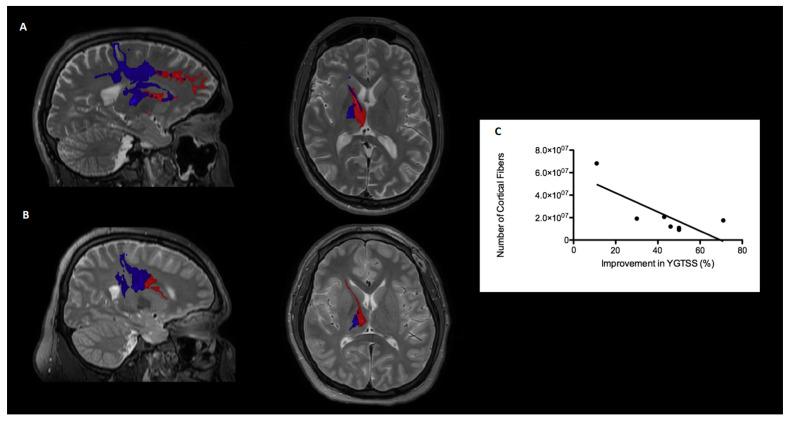

Probabilistic tractography in Tourette syndrome (TS) patients have shown an alteration in the connectivity of the primary motor cortex and supplementary motor area with the striatum and thalamus, suggesting an abnormal connectivity of the cortico-striatum-thalamocortical-pathways in TS. Deep brain stimulation (DBS) of the centromedian nucleus-nucleus ventrooralis internus (CM-Voi complex) in the thalamus is an effective treatment for refractory TS patients. We investigated the connectivity of activated fibers from CM-Voi to the motor cortex and its correlation between these projections and their clinical outcome. Seven patients with TS underwent CM-Voi-DBS surgery and were clinically evaluated preoperatively and six months postoperatively. We performed diffusion tensor imaging to display the activated fibers projecting from the CM-Voi to the different motor cortex regions of interest. These analyses showed that the extent of tic reduction during DBS is associated with the degree of stimulation-dependent connectivity between CM-Voi and the motor cortex, and in particular, an increased density of projections to the presupplementary motor area (preSMA). Non-responder patients displayed the largest amount of active fibers projecting into cortical areas other than motor cortex compared to responder patients. These findings support the notion that an abnormal connectivity of thalamocortical pathways underlies TS, and that modulation of these circuits through DBS could restore the function and reduce symptoms.

对图雷特综合征(TS)患者进行的概率性纤维束成像显示,初级运动皮层和辅助运动区与纹状体和丘脑之间的连接性发生了改变,这表明TS患者的皮质-纹状体-丘脑-皮质通路存在异常连接。对丘脑中央中核-腹内侧核(CM-Voi复合体)进行深部脑刺激(DBS)是治疗难治性TS患者的一种有效方法。我们研究了从CM-Voi激活的纤维与运动皮层之间的连接性,以及这些投射与临床结果之间的相关性。7例TS患者接受了CM-Voi-DBS手术,并在术前和术后6个月进行了临床评估。我们进行了扩散张量成像,以显示从CM-Voi投射到不同感兴趣运动皮层区域的激活纤维。这些分析表明,DBS期间抽动减少的程度与CM-Voi和运动皮层之间刺激依赖性连接的程度相关,特别是与投射到补充运动前区(preSMA)的密度增加有关。与有反应的患者相比,无反应的患者显示投射到运动皮层以外皮质区域的活性纤维数量最多。这些发现支持了这样一种观点,即丘脑皮质通路的异常连接是TS的基础,并且通过DBS对这些回路进行调节可以恢复功能并减轻症状。